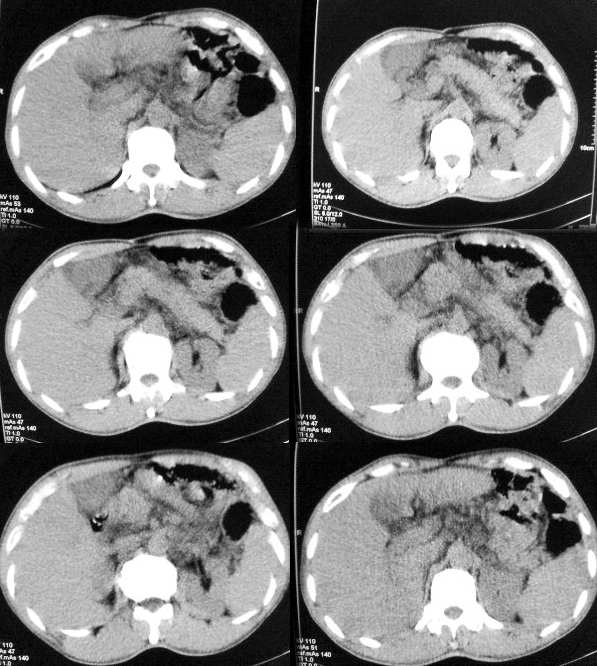

以下是引用butterylf在2005-12-21 19:10:00的发言:[br]我扫出来的图像都是这样的,窗宽窗位我参考了别的医院的啊,可是为什么我扫出来的图像质量不好,不好意思,是从显示器上拍的,而且还是用手机拍的,我不知道其他还能有什么方法拍啊!![br]病人是男性,41岁,[br]另外mas怎么调,不是不同的部位都要重新调过吧,?[br][br][br]对了,各位老师,我想问一个问题,我现在扫描片子打不出来了,这是为什么?ct已经传送过去了,可是激光打印就是出不来啊,打印机上总是显示close lower cover?这是为什么啊?